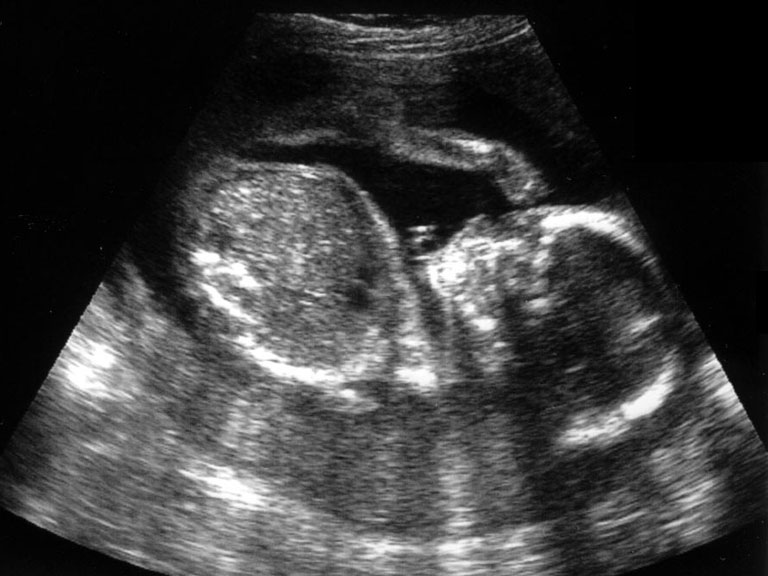

2분기 (임신 14주부터 28주)와 3분기 (임신 28주부터 출산까지)

1. 태아의 수

2. 태아의 선진부 (즉 머리가 산모의 골반쪽에 위치하는지 배꼽 쪽에 위치하는지 여부)

3. 태아의  생존 여부 즉 심박동 유무와 횟수 확인

4. 태반의 위치

5. 양수의 양

6. 태아 머리둘레와 대퇴골, 복부 측정으로 태령 및 태아 체중 예상

7. 제대의 착상 부와 혈관 구조 확인

8. 태아의 해부학적 구조 확인--뇌실, 심장, 척추, 위, 방광, 복벽, 신장등

9. 태아의 호흡이나 운동성 확인

10. 자궁과 그 부속기인 난소등 검사